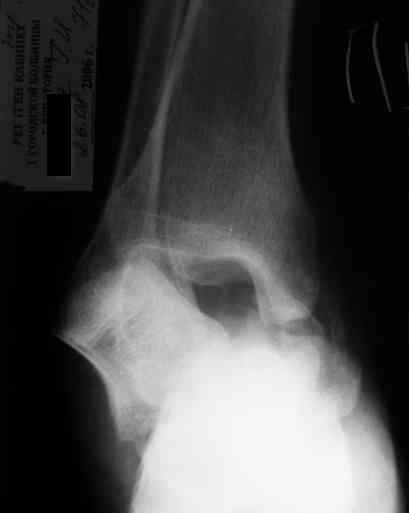

Re: Редкое повреждение - полный вывих тарана!

Уважаемый Александр! Как обещал представляю Р-граммы и операционные фото.

Ваши (лично ваши) рекомендации - астрагалэктомия-аппаратный пяточно-большеберцовый артродез с одновременным удлинением голени - правильно?